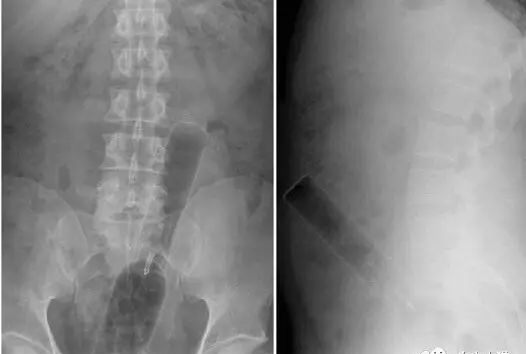

而面对这种直肠内有手机的优秀X光片,医生大概只能猜测,该病人可能是想测试这部诺基亚经典款卓越的超长待机、超频震动以及超强防水功能……对不起,编不下去了。

鉴于以上的人类迷惑行为,一名肛肠科医生见过了如此精彩纷呈的人体异物后,再看到什么都会见怪不怪了,于是这就考验着医生的另一项专业能力——编剧能力——如何能在不让病人家属知道真相的同时解释清楚这神奇的X光片。